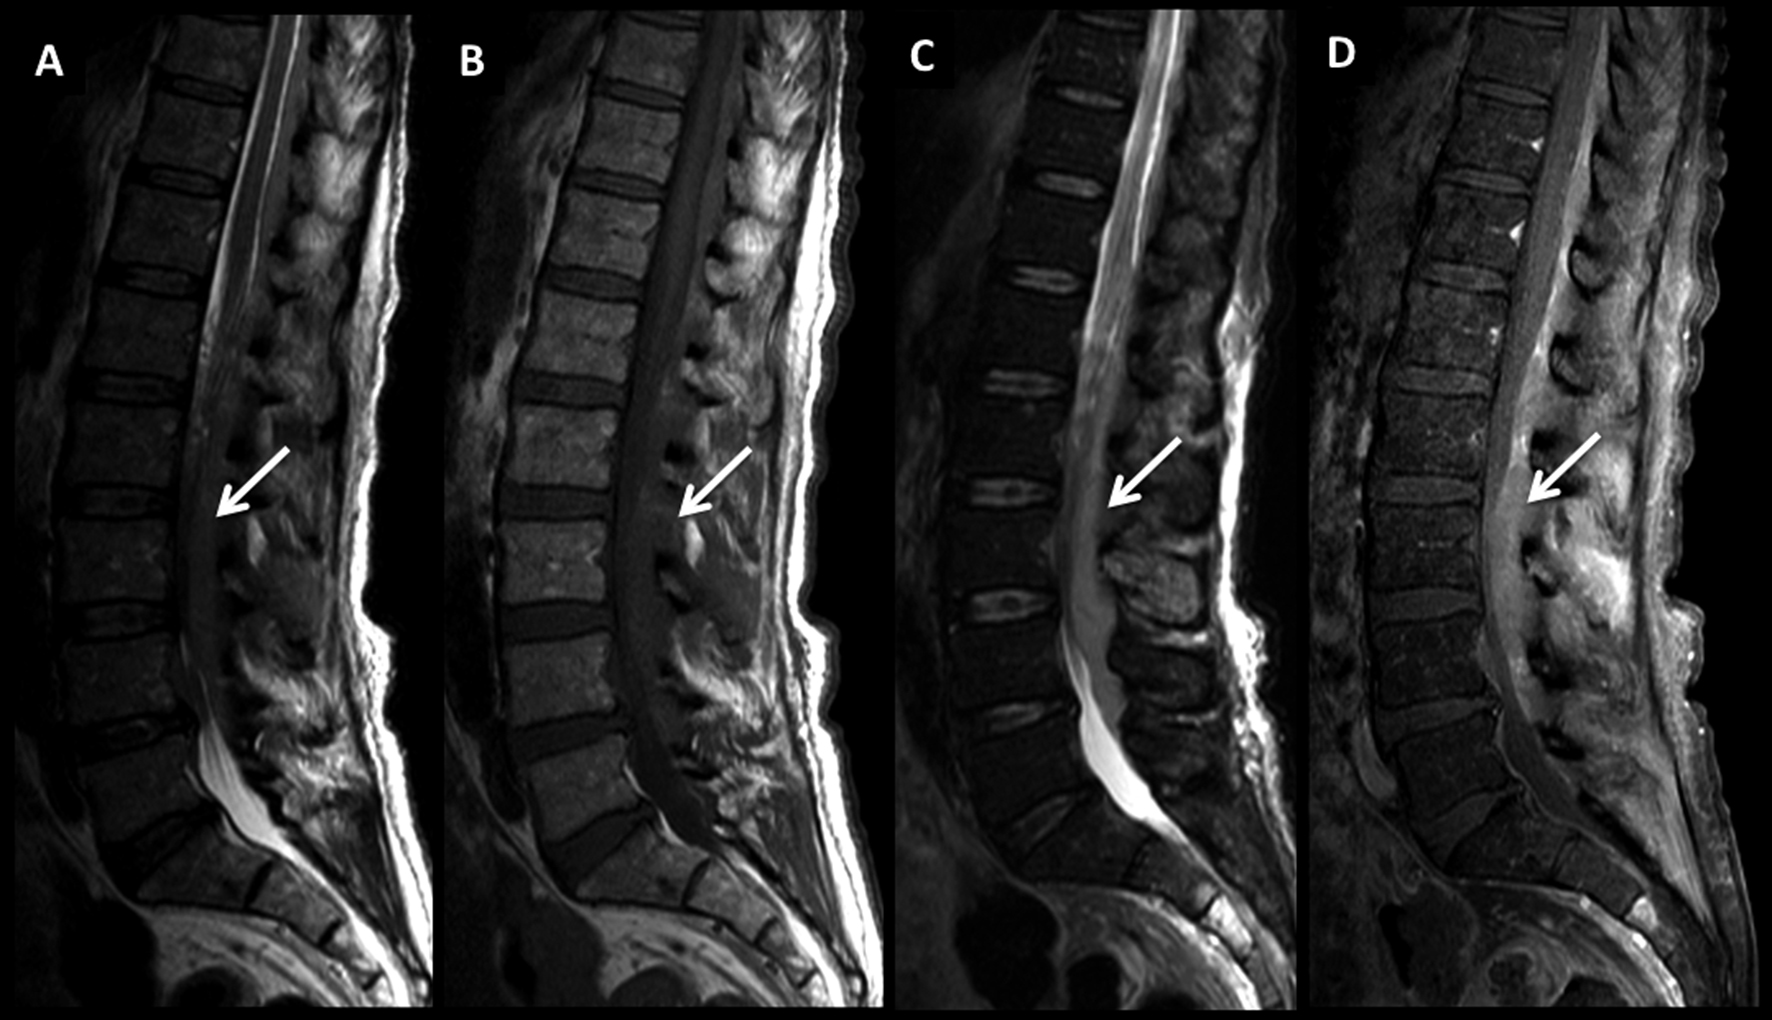

Figura 3

LNH, lesión ósea única, compromiso secundario. (cont)

En el paciente se observa un patrón de lesiones múltiples de sustitución con un patrón infiltrativo. En la TC plano sagital (A) se observa un aumento difuso, parcheado de la densidad, sin aplastamientos vertebrales.

En RM, secuencia T2 sagital (B) las lesiones están mal definidas con alta señal, hipointensas en secuencia T1 (C) y edema en secuencia STIR (D).

Este patrón, menos frecuente, tiene diferentes diagnósticos diferenciales, sobre todo con el mieloma múltiple.

Figura 5

LNH, lesiones óseas múltiples y masa intrarraquídea extradural, compromiso secundario.

Paciente con diagnóstico de LNH sistémico y lesiones óseas múltiples (*) a nivel dorsal bajo y masa intrarraquídea extradural con compresión medular.

Las lesiones son de baja señal en T2 (A) y T1 (B) con edema óseo en STIR (C) y realce intenso, algo heterogéneo con el medio de contraste (D).

La masa intrarraquídea es sólida con intenso realce y que comprime el cordón medular. En secuencia T1 en fase (E) y fuera de fase (F) se observa el comportamiento habitual de las lesiones agresivas, con aumento de señal en el pasaje de una fase a la otra. En difusión b1000 (G) y mapa de ADC (H) las lesiones son de alta y baja señal respectivamente, un elemento habitual en lesiones agresivas.